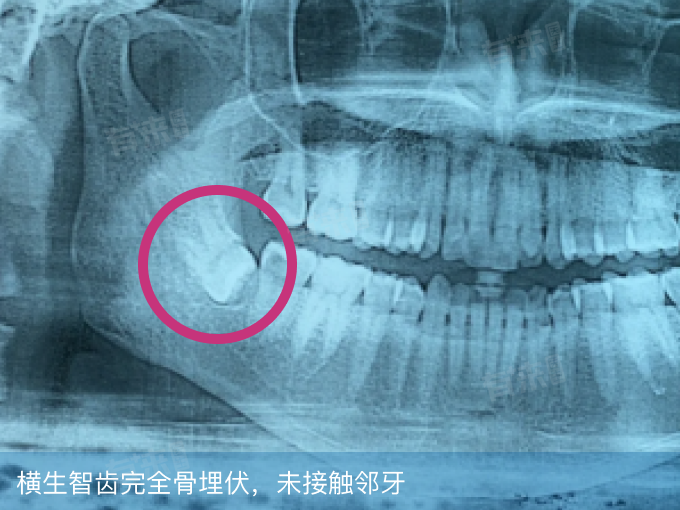

智齿横着长在属于阻生牙的一种类型,指智齿在萌出过程中,受多种因素影响,牙体长轴与第二磨牙长轴呈近乎90度横向生长,无法正常萌出至咬合位置。智齿横着长可能是遗传因素影响、颌骨空间不足、萌出顺序异常、邻牙阻力干扰等原因引起的。

2、颌骨空间不足:人类在进化过程中,颌骨逐渐退化变小,而智齿作为最后萌出的牙齿,往往缺乏足够的萌出空间。当牙槽骨容纳不下智齿正常直立生长所需空间时,智齿为寻求萌出路径,就会横向生长以占据有限空间,这是水平阻生智齿形成的主要原因。